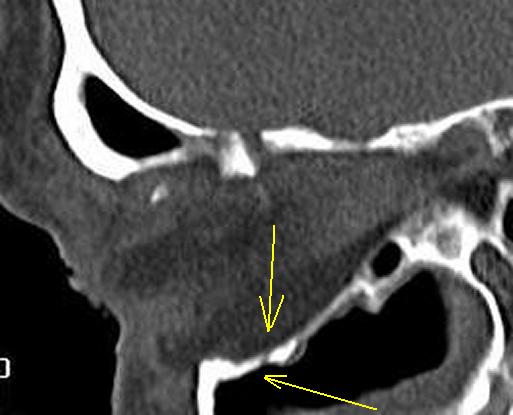

А это перелом или "естественное отверстие"?

Желтые стрелки - это оскольчатый перелом, зеленая - костный отломок, сместившийся в орбиту. Там, где красные стрелки переломов нет. По нижней стенке орбиты инфраорбитальная борозда, переходящая в инфраорбитальное отверстие, открывающееся кпереди ниже нижнего края орбиты.